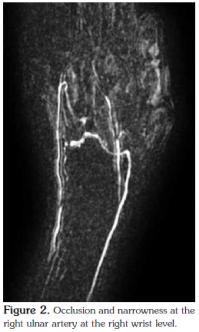

An arterial duplex Doppler ultrasound of the upper extremities showed a bilateral weak monophasic flow in the radial and ulnar arteries, and magnetic resonance angiography (MRA) of the upper extremities revealed that the right ulnar artery was occluded and narrowed at the level of the wrist (Figure 2). However, the left arm vessels and proximal vasculature on the right side were normal.